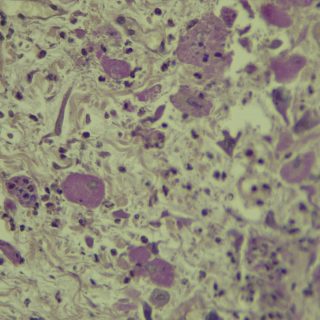

A vírus a csípést követően a bőrben elszaporodik, majd bekerül a véráramba, és a belső szervekben egy ismételt szaporodás után végül újra a bőrbe jut. Itt kialakulnak a klasszikus elváltozások, amelyek lényegében göbképződéssel járó gyulladásnak felelnek meg. A kórokozó hatására az irharétegben kialakulnak az ún. myxomasejtek (a myxomasejtek a mesenchyma-sejtekből kialakuló, nagy, sokszor nyúlványokkal rendelkező, módosult sejtek, amelyek tipikusak a myxomatosisban elhullott állatok irha rétegében) is. Az eddigi megfigyeléseink szerint a göbök a legintenzívebben a szemhéjakon, a száj körüli bőrképletekben és a genitáliákban jelennek meg, amelyet súlyosfokú vizenyő is kísér. Szövődményként gennyes jellegű orrgyulladás, bakokban tasakgyulladás és ivartól függetlenül kötőhártya-gyulladás is fellép, ami az érintett egyedek tájékozódási zavarával is jár. Mindennek eredményeként az állat lényegében képtelenné válik az életben maradásra: táplálkozása akadályozott, könnyű prédává válik a ragadozók számára és közútra tévedve gyakran a forgalom áldozatává válik.

Kutatóink a vizsgálataik során a jellegzetes kórbonctani és kórszövettani elváltozások mellett, PCR vizsgálattal a vírus örökítő anyagát is ki tudták mutatni. A vírus genom-szekvenálását követően pedig teljes bizonyossággal beigazolódott a kórkép okozta elhullás. Eredményeinket az országban elsőként az Acta Veterinaria Hungarica tudományos folyóirat hasábjain közöljük, amit a folyóirat már közlésre be is fogadott.